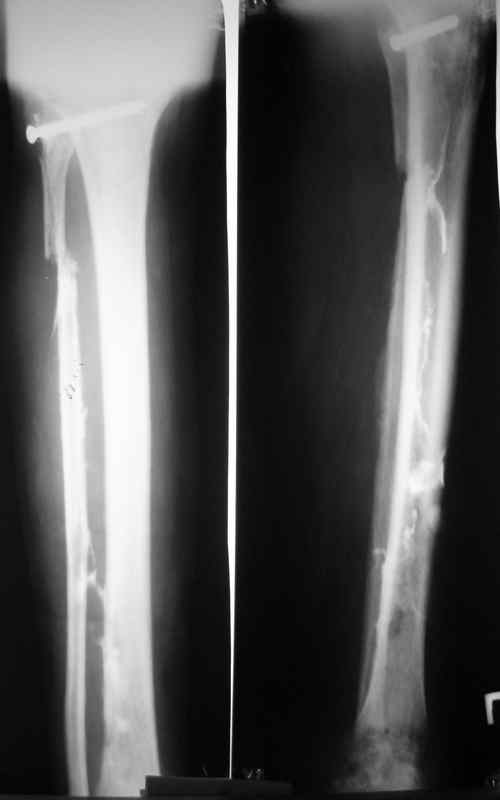

Доброго времени суток, коллеги! Сегодня поступил больной с остеомиелитом голени, 29 лет. Травма - январь 2007 года, <Открытый перелом малоберцевой кости,с повреждением малоберцевого нерва>. Первичных снимков нет. лечился в одной из районных больниц xUSSR. Обратился ко мне в сентябре 2007 года, сжалобами на наличие свищей,неопорность конечности.Был направлен после выполнения фистулографии (см. фото) в областной центр по лечению остеомиелита. Там была выполнено 2 операции: резекция малоберцевой кости, и повторный дебридмент. Последнее вмешательство около месяца назад. Послеоперационные снимки на фото. В течении месяца получал перевязки, и иньекции Бициллина- 5.Выписки больной не предоставил, вся информация с его слов. Опять же с его слов были рекомендованы перевязки с раствором димексида. На момент поступления раны и свищи хорошо видно на картинке, в дне раны кость жёлтого цвета, из раны гнойное отделяемое, с прямо таки неприятным запахом. (посев возьму завтра, но скорее всего там будет синегнойная, MRSA ). Стопа в эквинусе, активных движений нет, конечность неопорна. В связи с тем, что больной лечился в вышестоящей больнице, прошу скорректировать план лечения. Мой план: выполнить полноценный дебридмент, лаваж, <бусы>, рану зашить с дренажами по Редону. При выявлении поражения большеберцевой кости более 2\3 диаметра сегментарная резекция с последующим замещением дефекта по Илизарову. Активная ЛФК для голеностопа.

Конкретно по этому случаю достаточного впечатления не сложилось. Похоже, есть и внутриканальное распространение, так что, наверно, тут надо не

только бусы, или вообще не бусы, а в трубке силиконовой сделать с металлическим сердечником из тонкого стержня или 2-3 спиц.